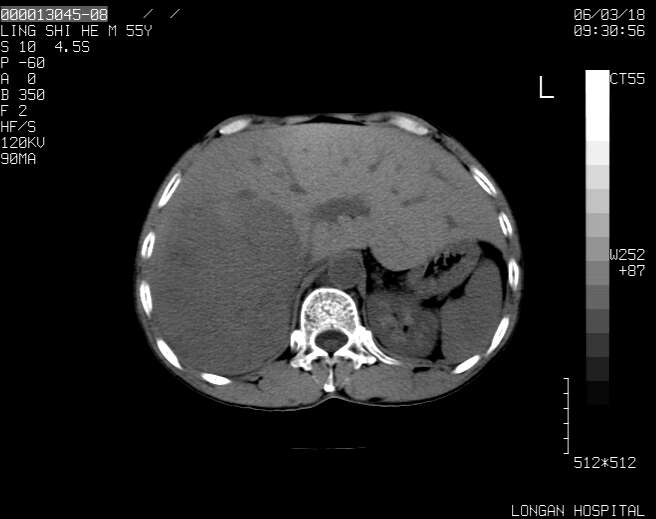

以下是引用guzhongliangddd在2006-3-21 22:13:00的发言:[br]病灶主要位于肝右叶的后份,内见异常血管,门脉主干及右支受侵{提示有癌栓形成},门腔间隙内见增大淋巴结。肝左叶内未见异常。

以下是引用zhuxinli在2006-3-22 1:23:00的发言:[br][br] 病灶主要位于肝右叶的后份,内见异常血管 .门脉右支截断,右叶前段早期强化(考虑动静脉漏),腹膜后肿大淋巴结,病灶逐渐强化,考虑为胆管细胞癌[br]